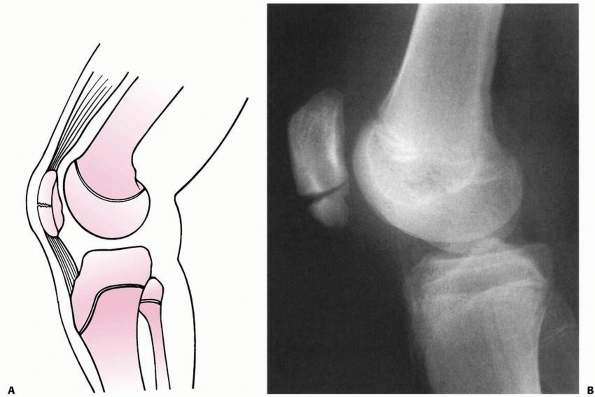

stress across the knee joint. In skeletally mature individuals, this

mechanism of injury can cause ligamentous disruption because ligaments

commonly fail before bone fails when a bending stress is applied across

the knee joint (Fig. 23-3A). However, loading

to failure across the immature knee is more likely to lead to physeal

failure due to tensile stresses that are transmitted through the

ligaments to the adjacent physis (Fig. 23-3B).45

FIGURE 23-3 A. In a skeletally mature patient with closed physis, tensile failure usually occurs across the ligament. B.

In a skeletally immature patient with open physis, failure usually occurs across the physis. (Reprinted with permission from Skaggs DL, Flynn JF. Trauma about the knee, tibia, and foot. In Skaggs DL, Flynn JF, eds. Staying out of Trouble in Pediatric Orthopaedics. Philadelphia: Lippincott Williams & Wilkins; 2006.) |